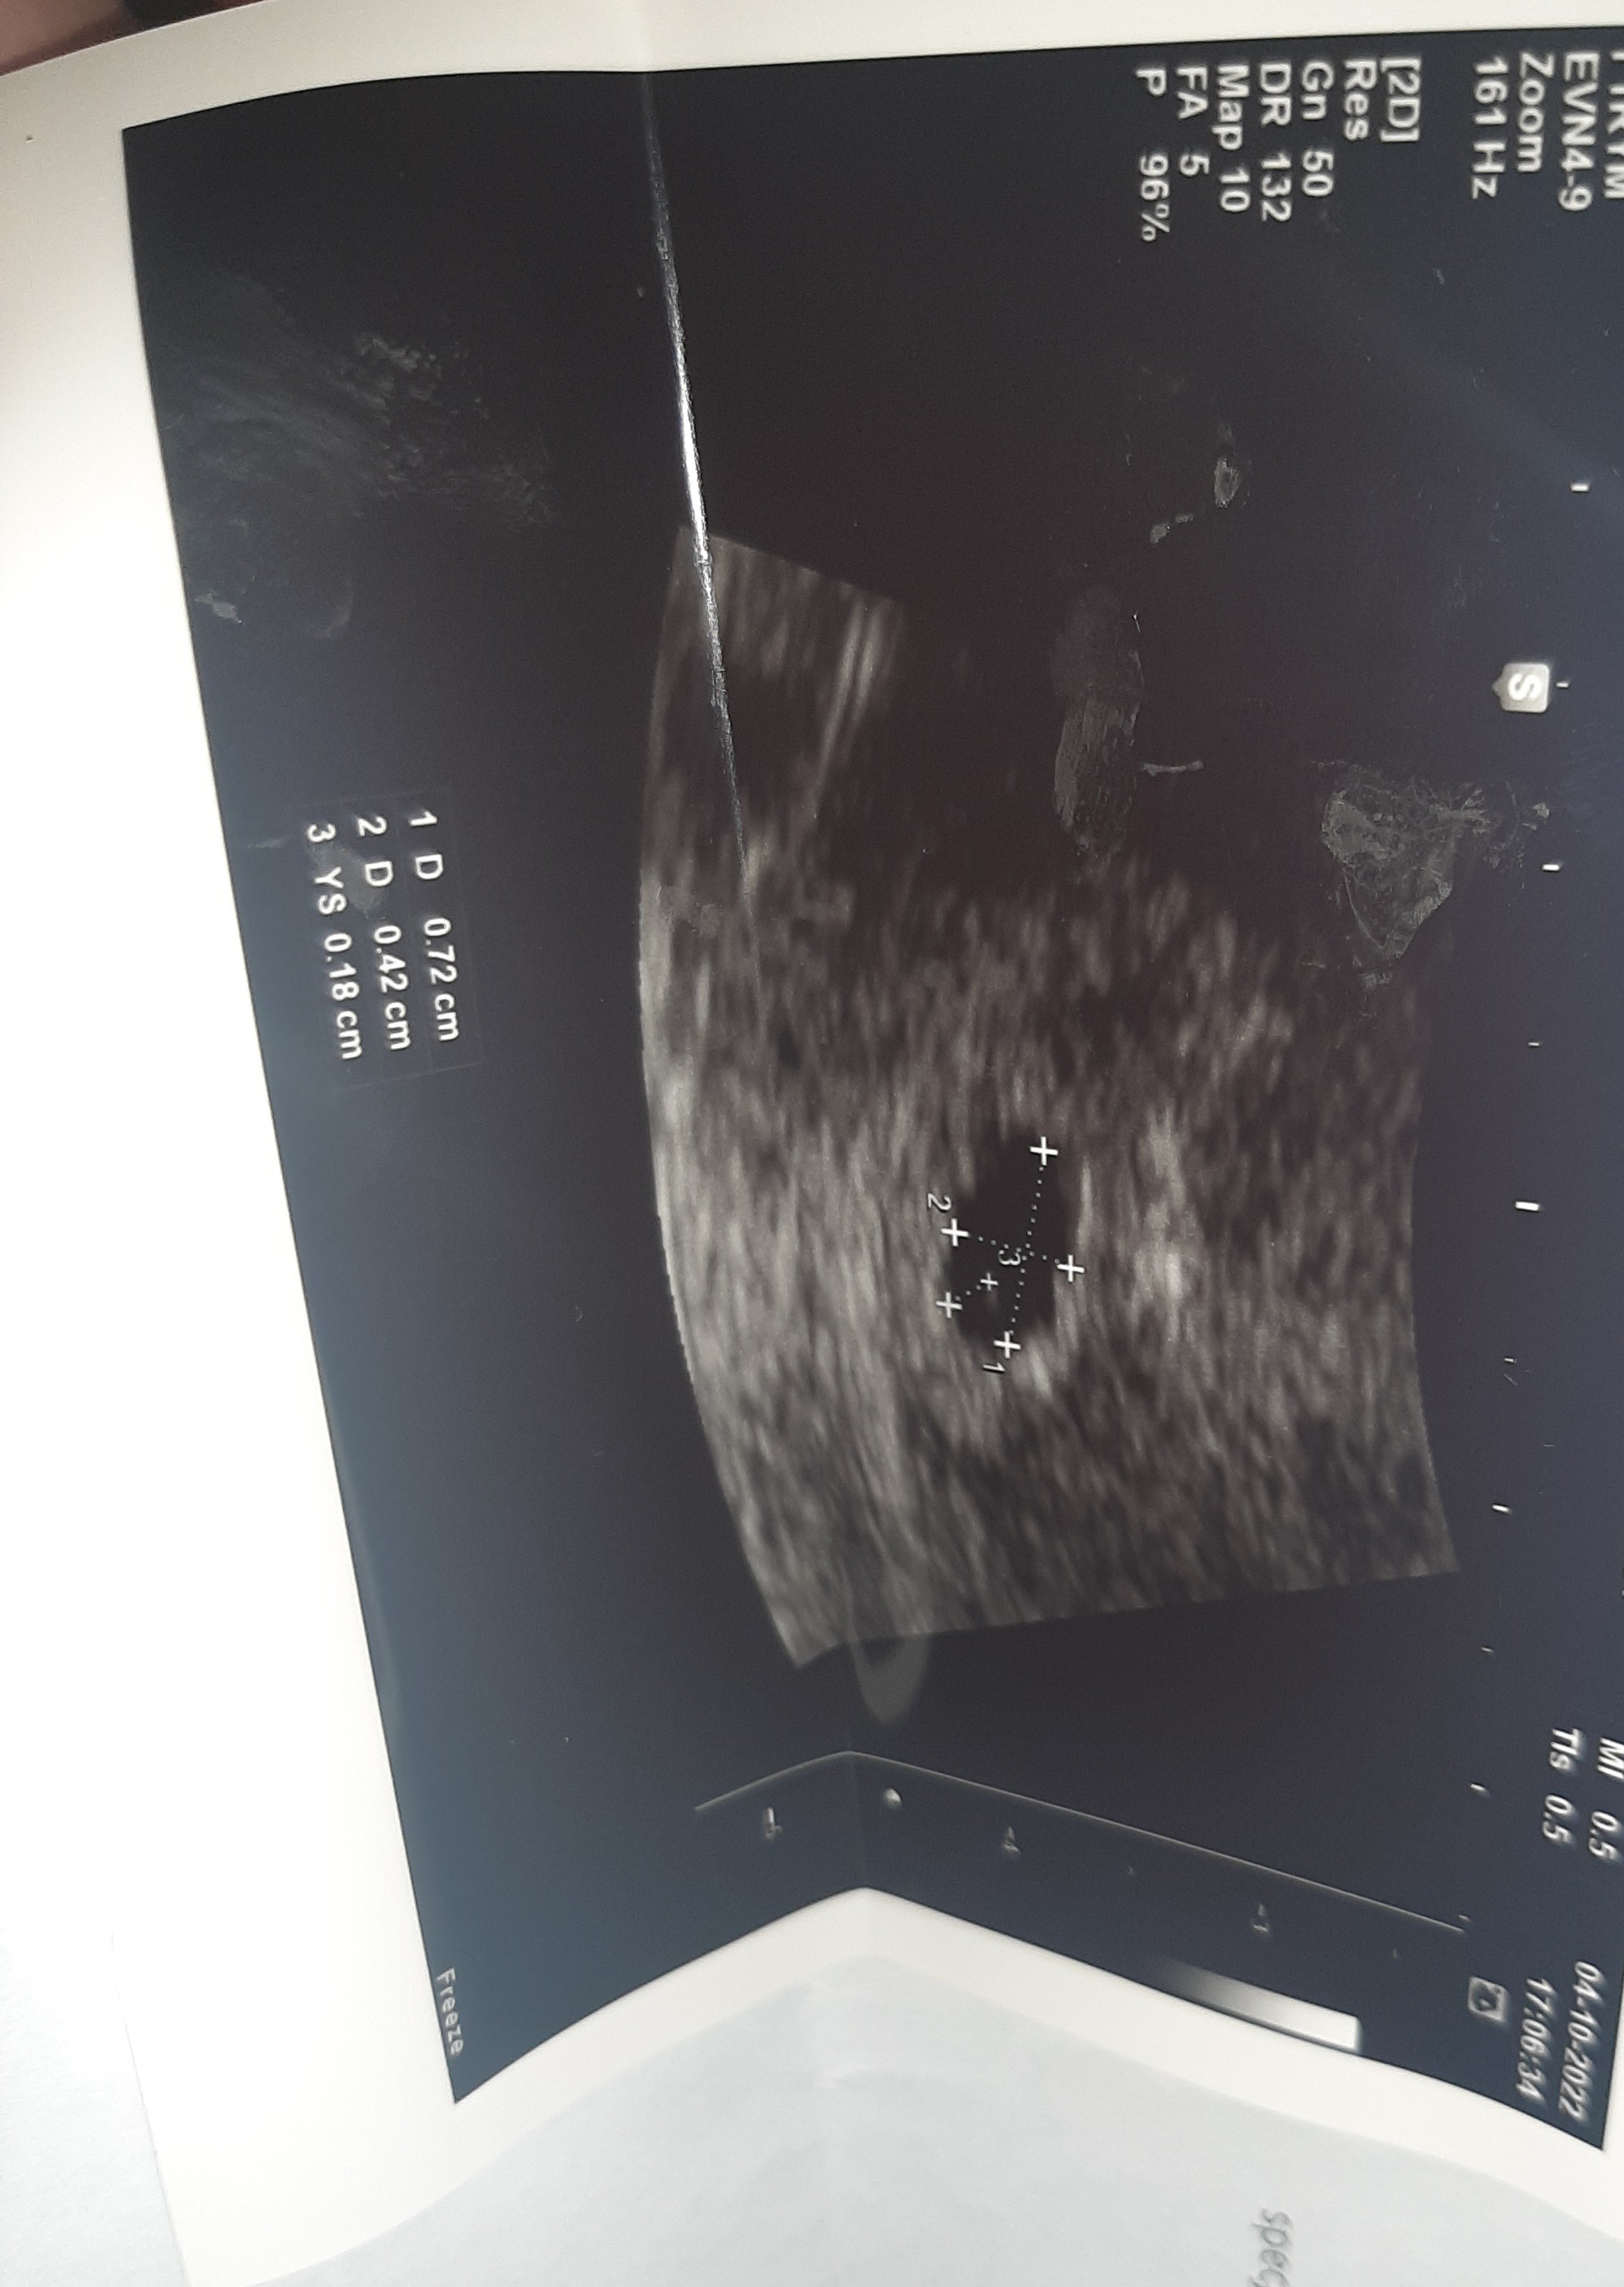

Po wizycie. Pęcherzyk ciążowy z pęcherzykiem zoltkowym, nastepna wizyta dopiero za 3 tygodnie. Na dzień dobry dostałam 25 eutyrox, w poprzedniej ciąży też brałam, a jeszcze później acard. L4 wypisał już ciążowe więc mam nadzieję że to dobry znak

Acard na wysokie ciśnienie. Tydzień przed porodem trafiłam do szpitala bo i tak było wysokie 165/95 i tak już zostałam do porodu. Dupa! Teraz patrzę i tam nie ma nic o pęcherzyku zoltkowym 😱

Załączniki

• 20221004_211331.jpg

20221004_211331.jpg

461,3 KB · Wyświetleń: 118